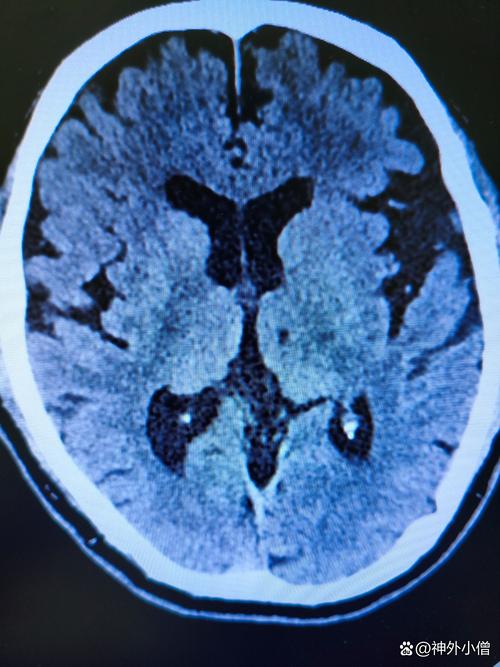

- 影像学检查证实病灶稳定:通过复查头颅CT或MRI(磁共振),可以看到梗塞的病灶已经“陈旧化”,周围的水肿已经完全消失,形成了一个小的软化灶,这个病灶会永久存在,但它已经不再“活跃”,不会继续扩大或产生新的损害。